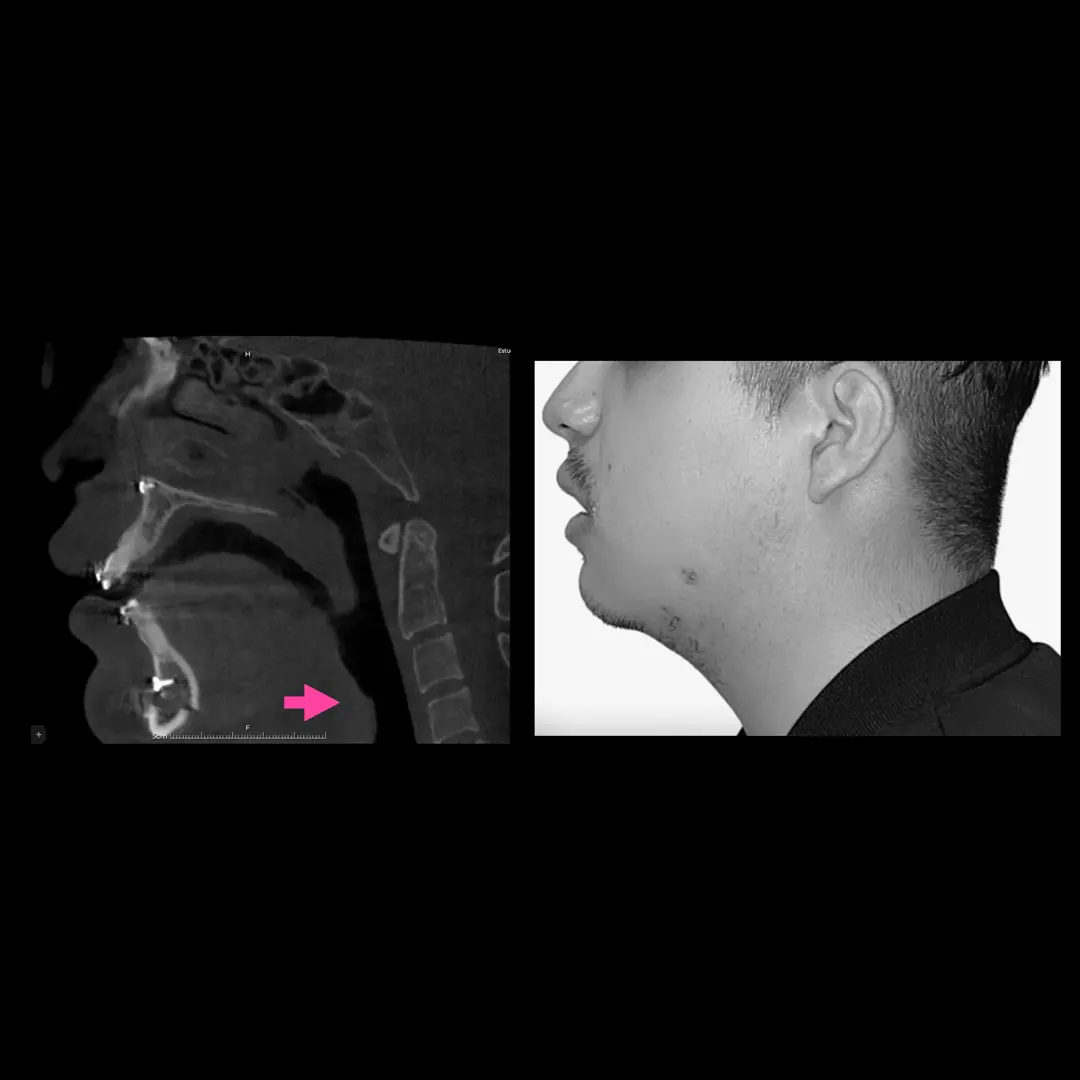

Apnea del sueño (por obstrucción maxilofacial)

Una de cada 10 personas adultas en México podría padecer apnea obstructiva del sueño, siendo este un factor de riesgo de hipertensión y enfermedades vasculares, los hombres presentan dos veces más probabilidad de padecer este problema.

Los neumólogos subrayan la necesidad de crear conciencia sobre la importancia de atender la apnea obstructiva del sueño, ya que, al ser común, las personas minimizan el problema por la creencia de que roncar es normal.

Los síntomas de la apnea son relativamente fáciles de identificar consisten en un ronquido continuo y ruidoso y pausas en la respiración al dormir.

La investigación del Síndrome de Apnea Obstructiva del Sueño, ha demostrado científicamente que la cirugía ortognática y/o de estructuras de los maxilares es una solución definitiva a este problema en pacientes que presentan deformidades dentofaciales.